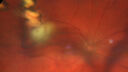

48 year old man: The patient saw the referring doctor 3-4 years ago with high IOP in the right eye. At the time there was a haze and floaters in the right eye. The IOP was 40+ (like it is today). The patient was on frequent drops at the time and that controlled the IOP. The vision returned and the floaters dissipated. The patient noticed new onset vision loss a few weeks ago. You noticed a retinal problem in addition to the high intraocular pressure. The floaters, high IOP and vision has been the right eye both times. On further questioning, he had vision loss in the right eye in 1990, 2017 and 2022 and ate a lot of venison in his youth in upstate NY. Medical/Surgical history: benign Systemic Meds: Vardenafil 5 MG Oral Tablet. VA OD: Dsc20/32 NscJ7 VA OS: Dsc20/16 NscJ1+ IOP: TP: OD:44 OS:27

Recurrent toxoplasmosis with elevated IOP35 views48 year old man with 4 episodes over 40 years of vision loss from toxoplasmosis. His IOP was 44 on presentation.